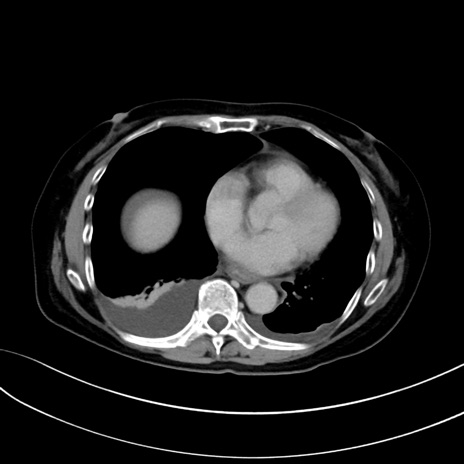

(冠状断像)1日半後